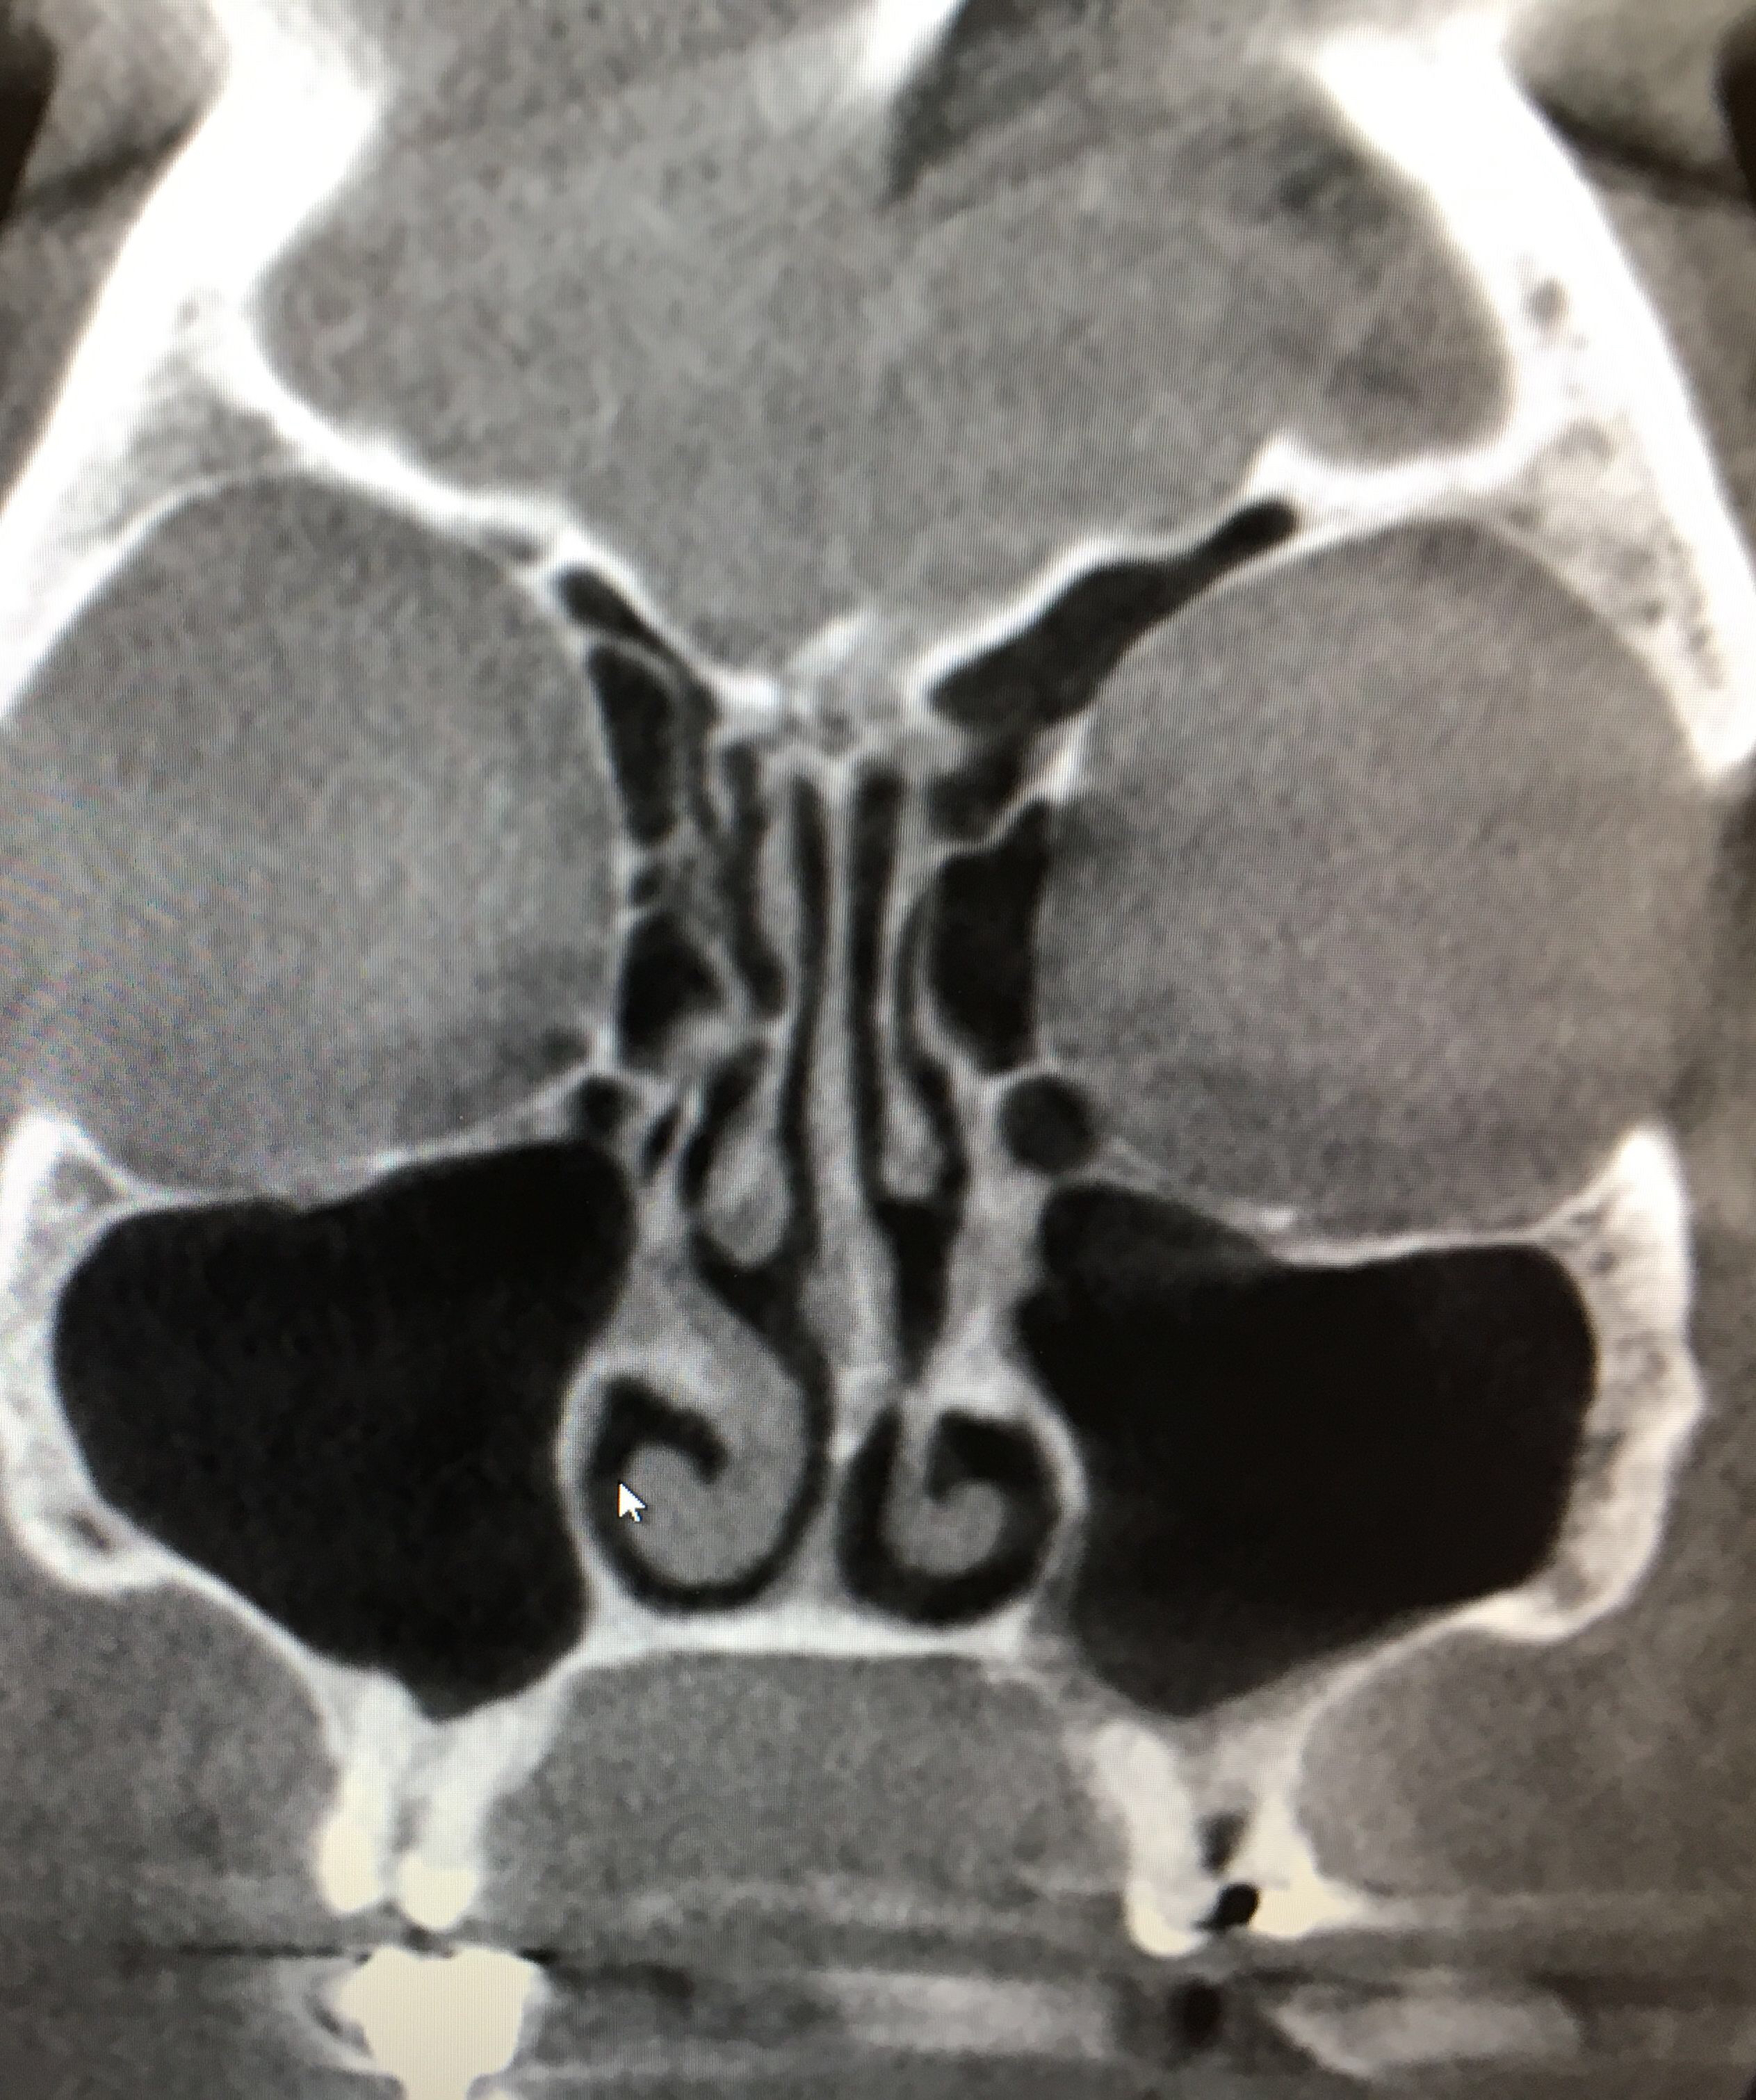

Cone beam CT is a much lower radiation 3D imaging technology that gives us a very clear picture of our sinuses as well as the cervical spine, temporomandibular joints, teeth, airway and bone.

These are two patients with identical symptoms, sinus and facial pressure that persisted and did not change with medication. Check out this video.

normal sinus versus filled left maxillary sinus

The take away from these two similar cases is that imaging was very helpful in establishing our diagnosis. One had no presence of sinus disease or infection but sinus pressure while the other had obvious signs of infection of multiple sinuses and was referred back to his ENT for a surgical consult. The underlying cause of the sinus pain without signs of sinus infection was determined to be the neck. Treatment to the neck resolved the patient’s symptoms.

If sinus pain is not responding to medical interventions and if the Cone Beam CT is negative check the neck. There are usually other signs present that the neck is not working optimally and the underlying cause.

How do you know you have a sinus infection? What if your pain and pressure continues even after antibiotics? A Cone Beam CT will show if you have a sinus infection or disease. If it shows that your sinuses are clear then your symptoms are being referred from your neck.